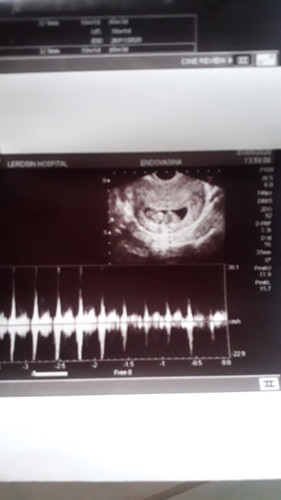

ครรภ์ประมาณ10สัปดาห์ฝากคลีนิกดันหาน้องไม่เจอแต่ไปรพ.เจอจ้าดีใจจนน้ำตาไหล